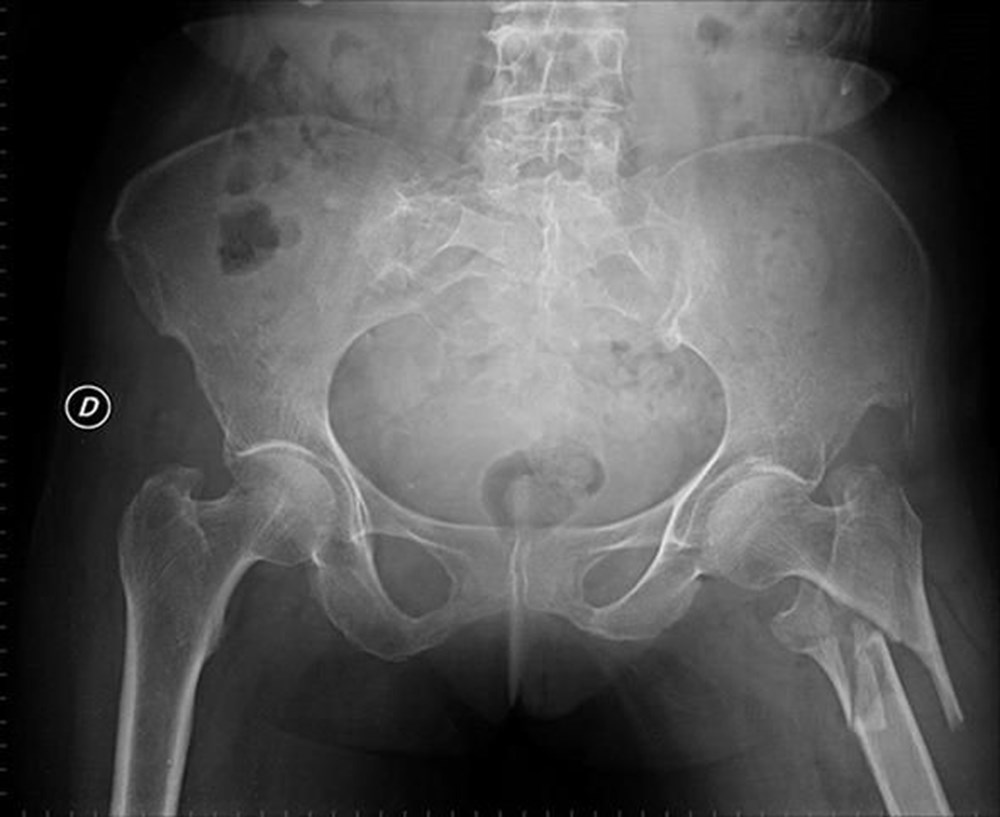

Рентгеновские снимки при остеопорозе